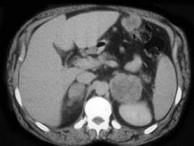

问题 男,56岁,有恶性黑色素瘤病史,请结合图像,作出诊断 ( )

选项 A、肾上腺转移瘤 B、肾上腺嗜铬细胞瘤 C、肾上腺髓样脂肪瘤 D、肾上腺癌 E、肾上腺腺瘤

答案 A